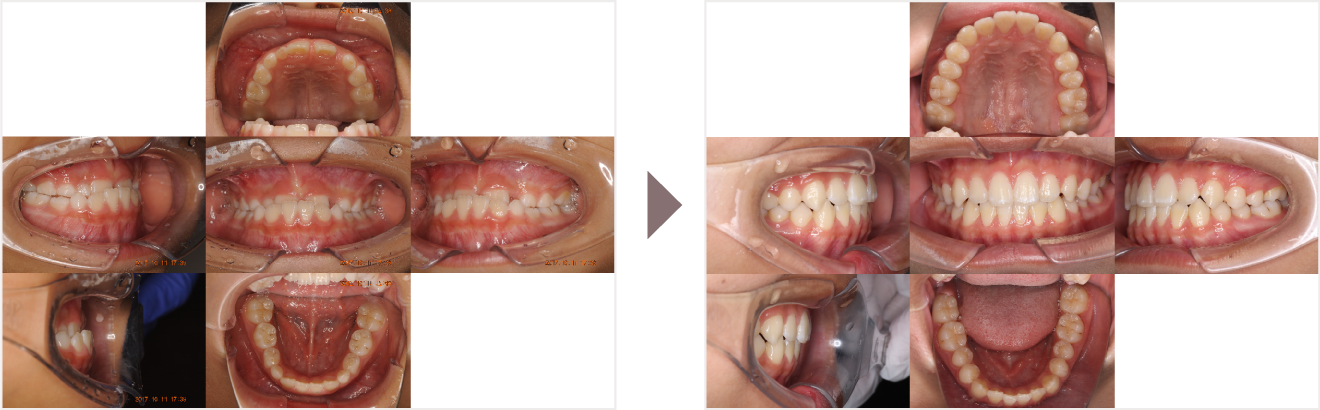

症例叢生

性別

期間6年10ヶ月

治療内容N-Bimler装置、Neo-Capを使用して治療

治療における

副作用・リスク

装着しないと効果は出ません

金額ビムラー装置:550,000円

ネオキャップ:8本

合計:594,000円